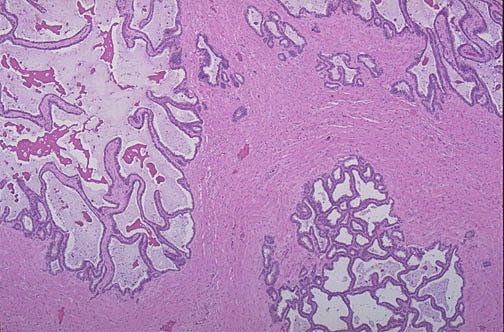

Normal seminal vesicle is composed of complex clusters of glandular channels with intervening fibromuscular stroma as seen here at low power.